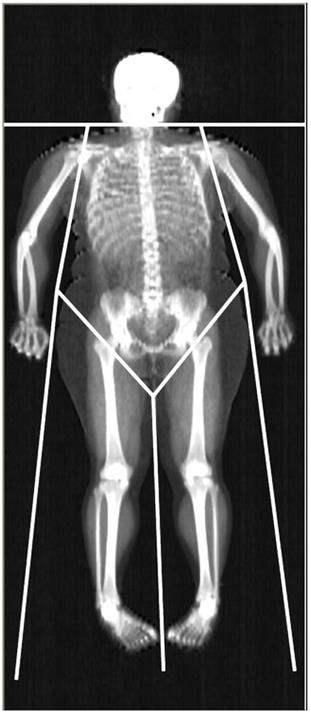

Dual-energy X-ray Absorptiometry (DXA) is able to accurately assess lean mass (distinguishing between the mass of lean soft tissue, LST, and mineral mass) at the whole body (WB) and regional level. The areal BMD is also included in the standard DXA output. The limb LST mass, BMC, and BMD can be easily obtained from DXA readings (Fig. 1). The sum of LST mass in the four limbs i.e., appendicular LST mass is used as a surrogate of skeletal muscle mass, and DXA estimates of appendicular LST mass have been validated against skeletal muscle mass measurements obtained with magnetic resonance imaging and computed tomography [3, 12, 13]. As far as muscle strength is concerned, isotonic muscle strength can be measured using several techniques, one of the most commonly used being the One Repetition Maximum (1-RM) technique. The Repetition Maximum represents the maximum number of repetitions performed before fatigue prohibits completion of an additional repetition and generally reflects the intensity of the exercise [14]. However, both DXA and 1-RM are laboratory-based techniques, which are unpractical for use in large or field studies due to their relatively high costs and logistics required to perform measurements. Further, DXA employs X-ray radiation, which may hamper its widespread use, and 1-RM may be harmful to joint and muscle when measuring maximum muscle strength in persons with low muscular strength. According to the considerations above, there is a need for a non-invasive, cheap, and repeatable tool to estimate lean mass components and muscle strength in obesity.

Representative whole-body DXA scan. The limits defining the regions of interest used in this work (upper and lower limb, trunk) are depicted.

For the standard regional body composition estimations, Hologic software readings divided the body into trunk, entire upper limb, entire lower limb, and head (Fig. 1).